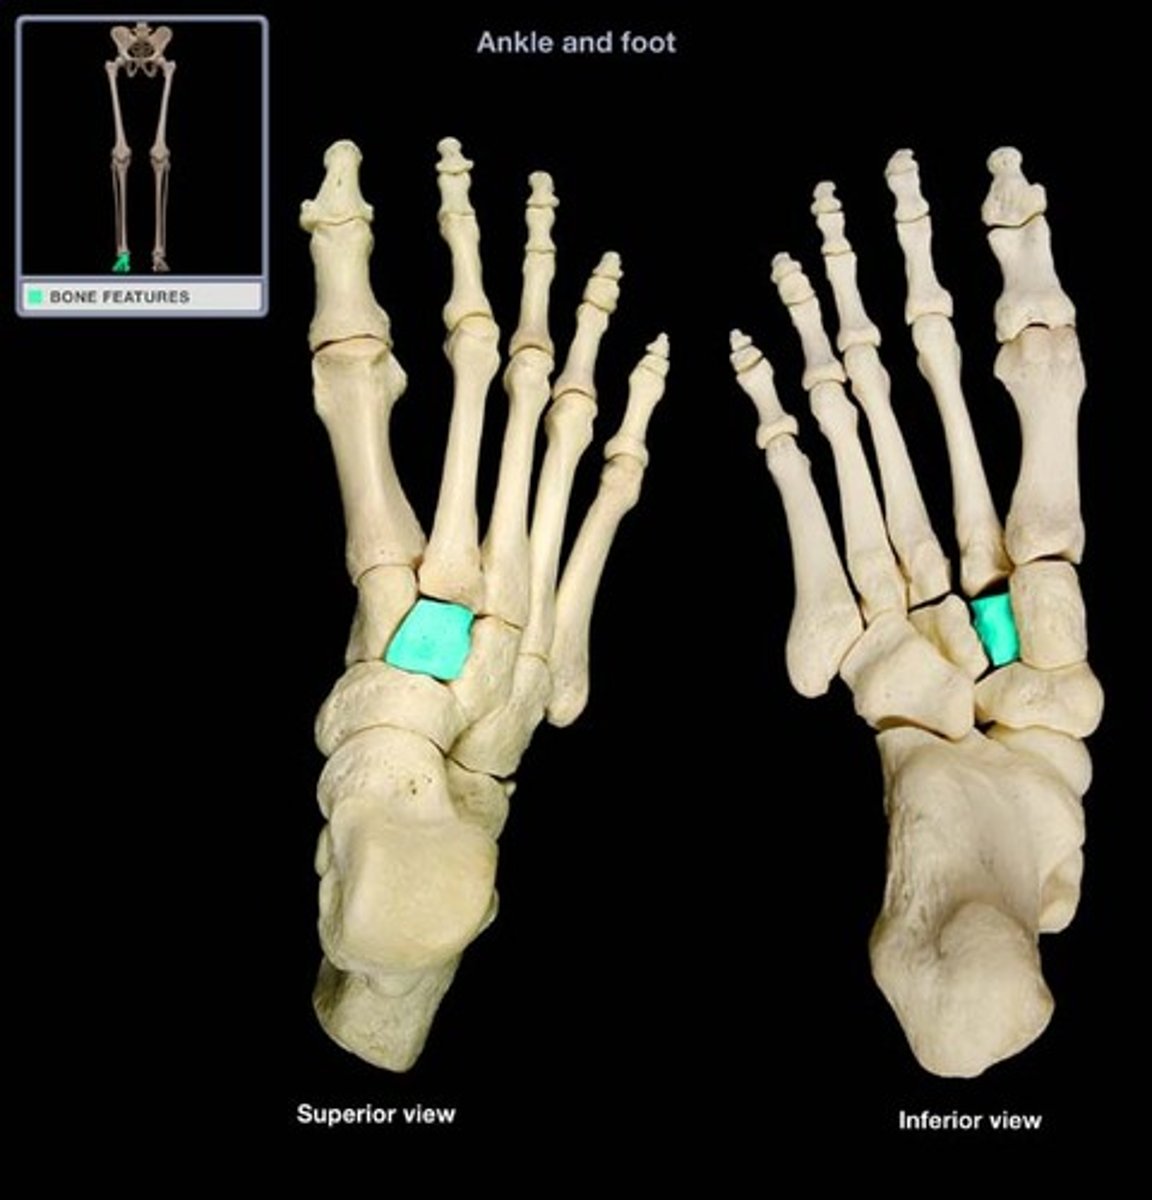

Medial cuneiform